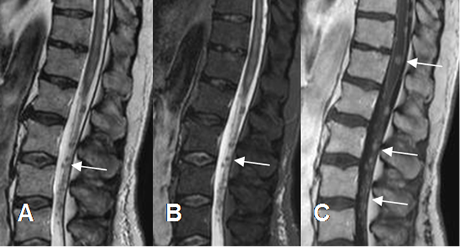

Fig 238. Diseminación leptomeningea.

A: RM sagital en T2, B: RM sagital en STIR y C: RM sagital en T1 con contraste. Imágenes redondeadas y de defecto de llenado, sobre la medula distal y las raíces de la cola de caballo, que realzan con el contraste y corresponden a diseminación leptomeningea, por un linfoma.